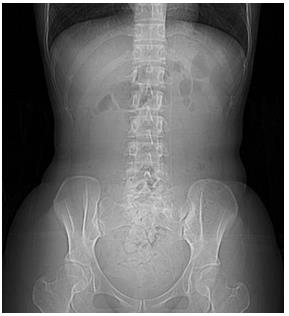

患者诉求:2周未排便。一个月前刚生产。无腹痛。进行了腹部X线检查(照片5)

腹中大便呈巨大茧状。

照片5:腹部X 线照片(卧位)

腹部正中间,从盆腔到横隔膜近傍位置有占位。横结肠内部有气体。“蝉蛹”左侧有颗粒状大便。是乙状结肠便。